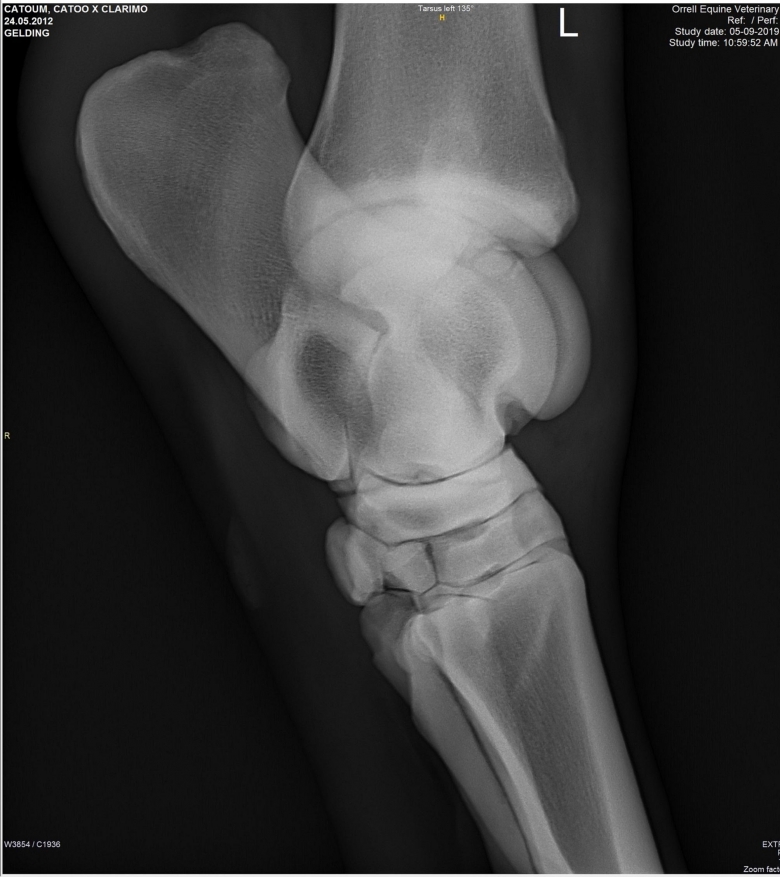

Snart dök det även upp röntgenplåtar, utan att Marina ens hade frågat efter dem. Röntgenbilderna skickade Marina vidare till två olika veterinärer för bedömning. Bägge såg lösa benbitar i ena hasen och Cecilia Grahn på Kungsbacka Hästklinik hade en mejlkonversation med den engelske veterinären ”Steve Orrell” som hade tagit bilderna. Att bilderna var falska och att det inte var den riktige Steve Orrell var det ingen som visste då. Han skrev att han hade sett hästen sedan den var tre år och argumenterade först emot de tre lösa benbitar som Cecilia Grahn hade hittat.

Lucas Bailey skickar bilder på röntgenplåtar. Marina Johansson låter två olika veterinärer bedöma bilderna. Bägge såg lösa benbitar i ena hasen och Cecilia Grahn på Kungsbacka Hästklinik hade en mejlkonversation med den engelske veterinären ”Steve Orrell” som hade tagit bilderna. ”Veterinären” skriver att han har sett hästen sedan den var tre år och argumenterar för att benbitarna saknar betydelse.